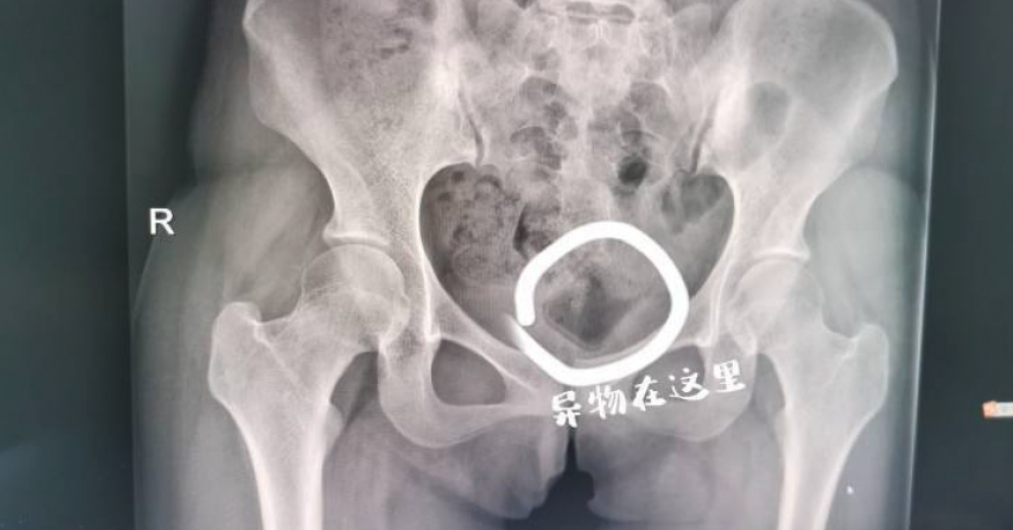

經檢查發現,瓶蓋表面光滑、無著力點,靠一般的醫療器材無法順利取出,所幸位置不算深,改用超音波引導,最終用手術鉗取出了小楊體內的異物,原來是個長5公分寬3公分、類似化妝品蓋子的東西。